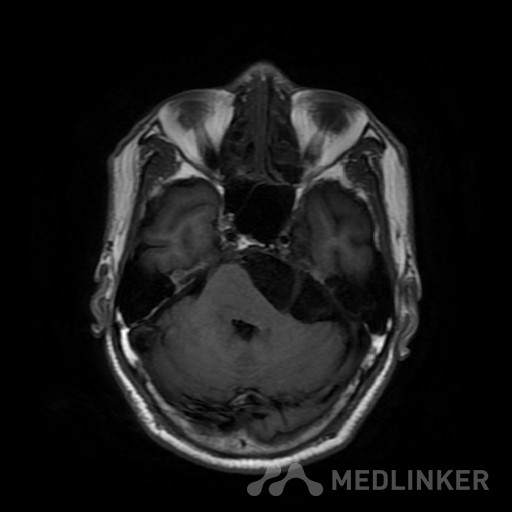

桥小脑区长T1长T2囊状病灶(如图),考虑表皮样囊肿还是蛛网膜囊

如图所示,左侧桥小脑区的囊状长T1长T2异常信号,增强扫描未见强化。考虑表皮样囊肿还是蛛网膜囊肿?